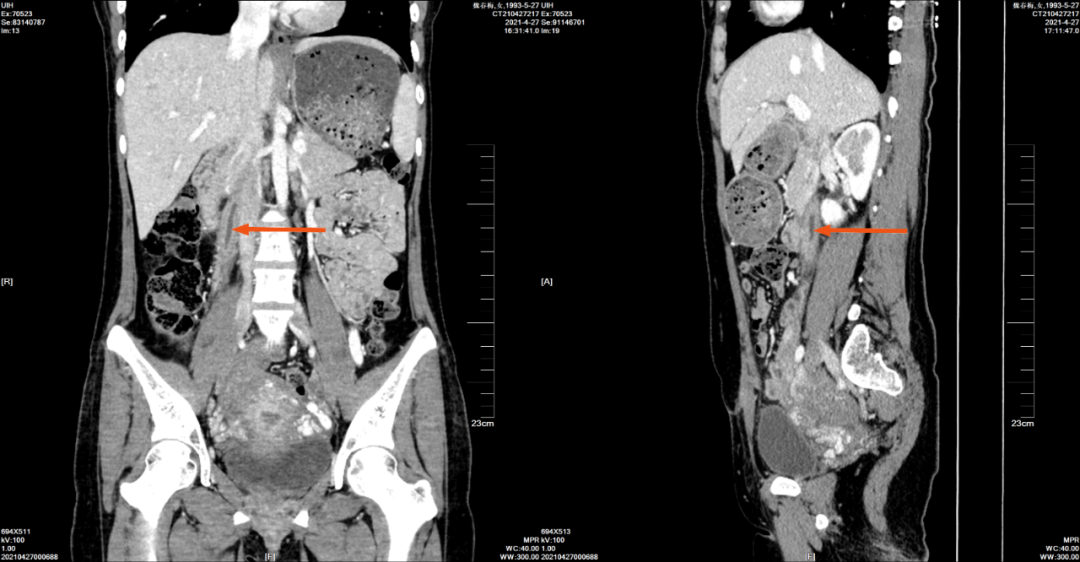

2021-4-27 腹部 CT 增强如下:

增强三期扫描图

增强门静脉期

冠状位与矢状位

右侧卵巢静脉明显增粗,管腔内可见充盈缺损,右侧卵巢静脉周围可见条片稍低密度影,增强扫描卵巢静脉壁呈明显渐进性强化影,周围见少许积液,较 CT210409-050 片其内密度有所减低,病灶周围渗出影有所减少,静脉增粗程度较前减轻。